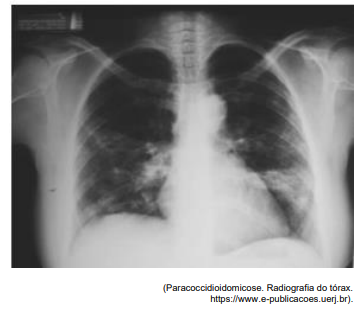

Analise a radiografia abaixo para responder à questão.